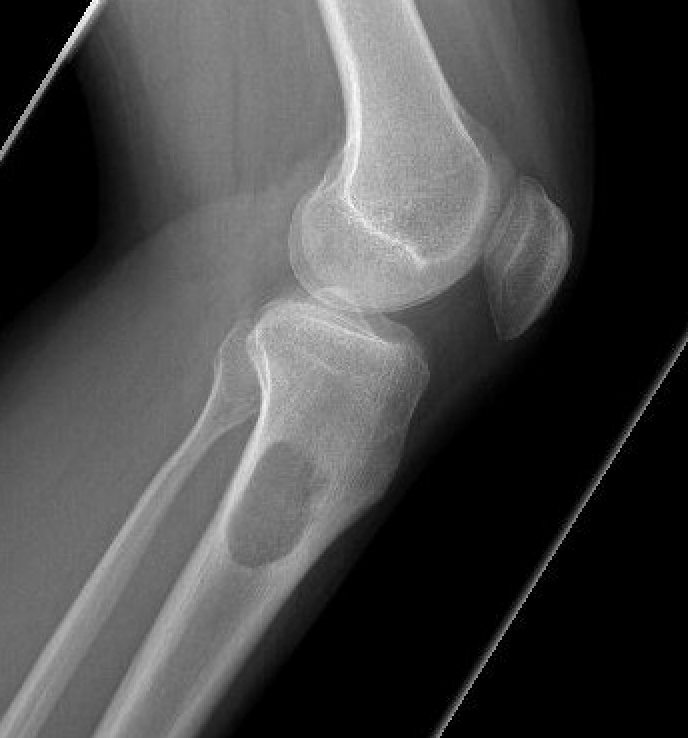

X-ray

Eccentrically located lucency in the metaphysis

- well-defined sclerotic margin

- local expansion but cortex intact